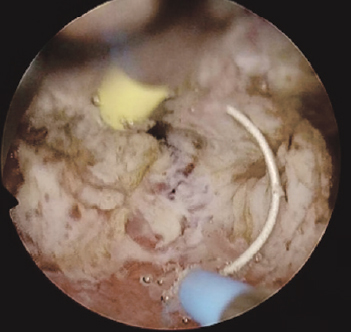

Принято решение о повторном оперативном лечении перкутанным доступом. В положении пациента на животе под эндотрахеальным наркозом выполнена пункция полостной системы правой почки через нижнюю группу чашек, пункционный тракт бужирован до 24 Ch и установлен кожух Амплатц. С помощью гибкого видеонефроскопа произведена ревизия полостной системы правой почки, в проекции зоны предыдущей резекции опухоли отмечается рубцово-измененная стенка лоханки, в области рубца рецидива новообразования не выявлено. При дальнейшей ревизии полостной системы правой почки в проекции верхних групп чашек выявлена крупная опухоль крупноворсинчатой структуры на широком основании (рис. 7). Выполнить ее резекцию не представлялось возможным из-за острого угла «атаки» и невозможности адекватно провести инструмент в верхнюю группу чашек. Принято решение о применении дополнительного перкутанного доступа в проекции верхних групп чашек. Под ультразвуковым и визуальным контролем прецизионно был произведен второй доступ в верхнюю группу чашек вблизи с новообразованием (рис. 8).

Рис. 7. Опухоль полостной системы правой почки, расположенная в проекции верхних групп чашек

Fig. 7. Tumor of the cavitary system of the right kidney located in the projection of the upper groups of calyces

Произведено бужирование пункционного хода до 28 Ch, в почечную лоханку заведен резектоскоп. Учитывая размер новообразования и его широкое основание было принято решение выполнить резекцию новообразования инструментом с биполярной подачей энергии (рис. 9).

Рис. 9. Этап резекции опухоли полостной системы почки с применением биполярного вида энергии

Fig. 9. Stage of resection of the tumor of the pelvicalyceal system of the kidney with a bipolar type of energy